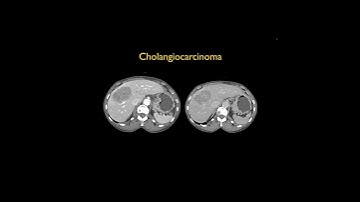

Cholangiocarcinoma | Resection